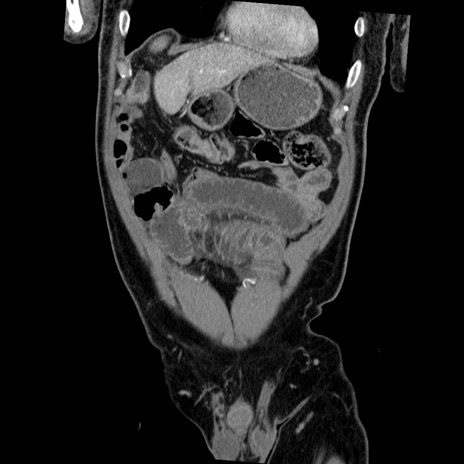

症例22(冠状断像)

【症例】50歳代男性

【主訴】腹痛

【現病歴】AVMからの被殻出血のため回復期リハ病棟入院中。 本日午後3時頃急に下腹部痛が出現した。

【既往歴】AVM、被殻出血、虫垂炎、高血圧

【身体所見】意識晴明、左半身不全麻痺、会話の理解は良好、36.5°C、腹部:膨隆、全体に板状硬、下腹部正中に圧痛点あり、反跳痛-、筋性防御不明、右下腹部にope scar

【データ】WBC 9400、CRP 0.06